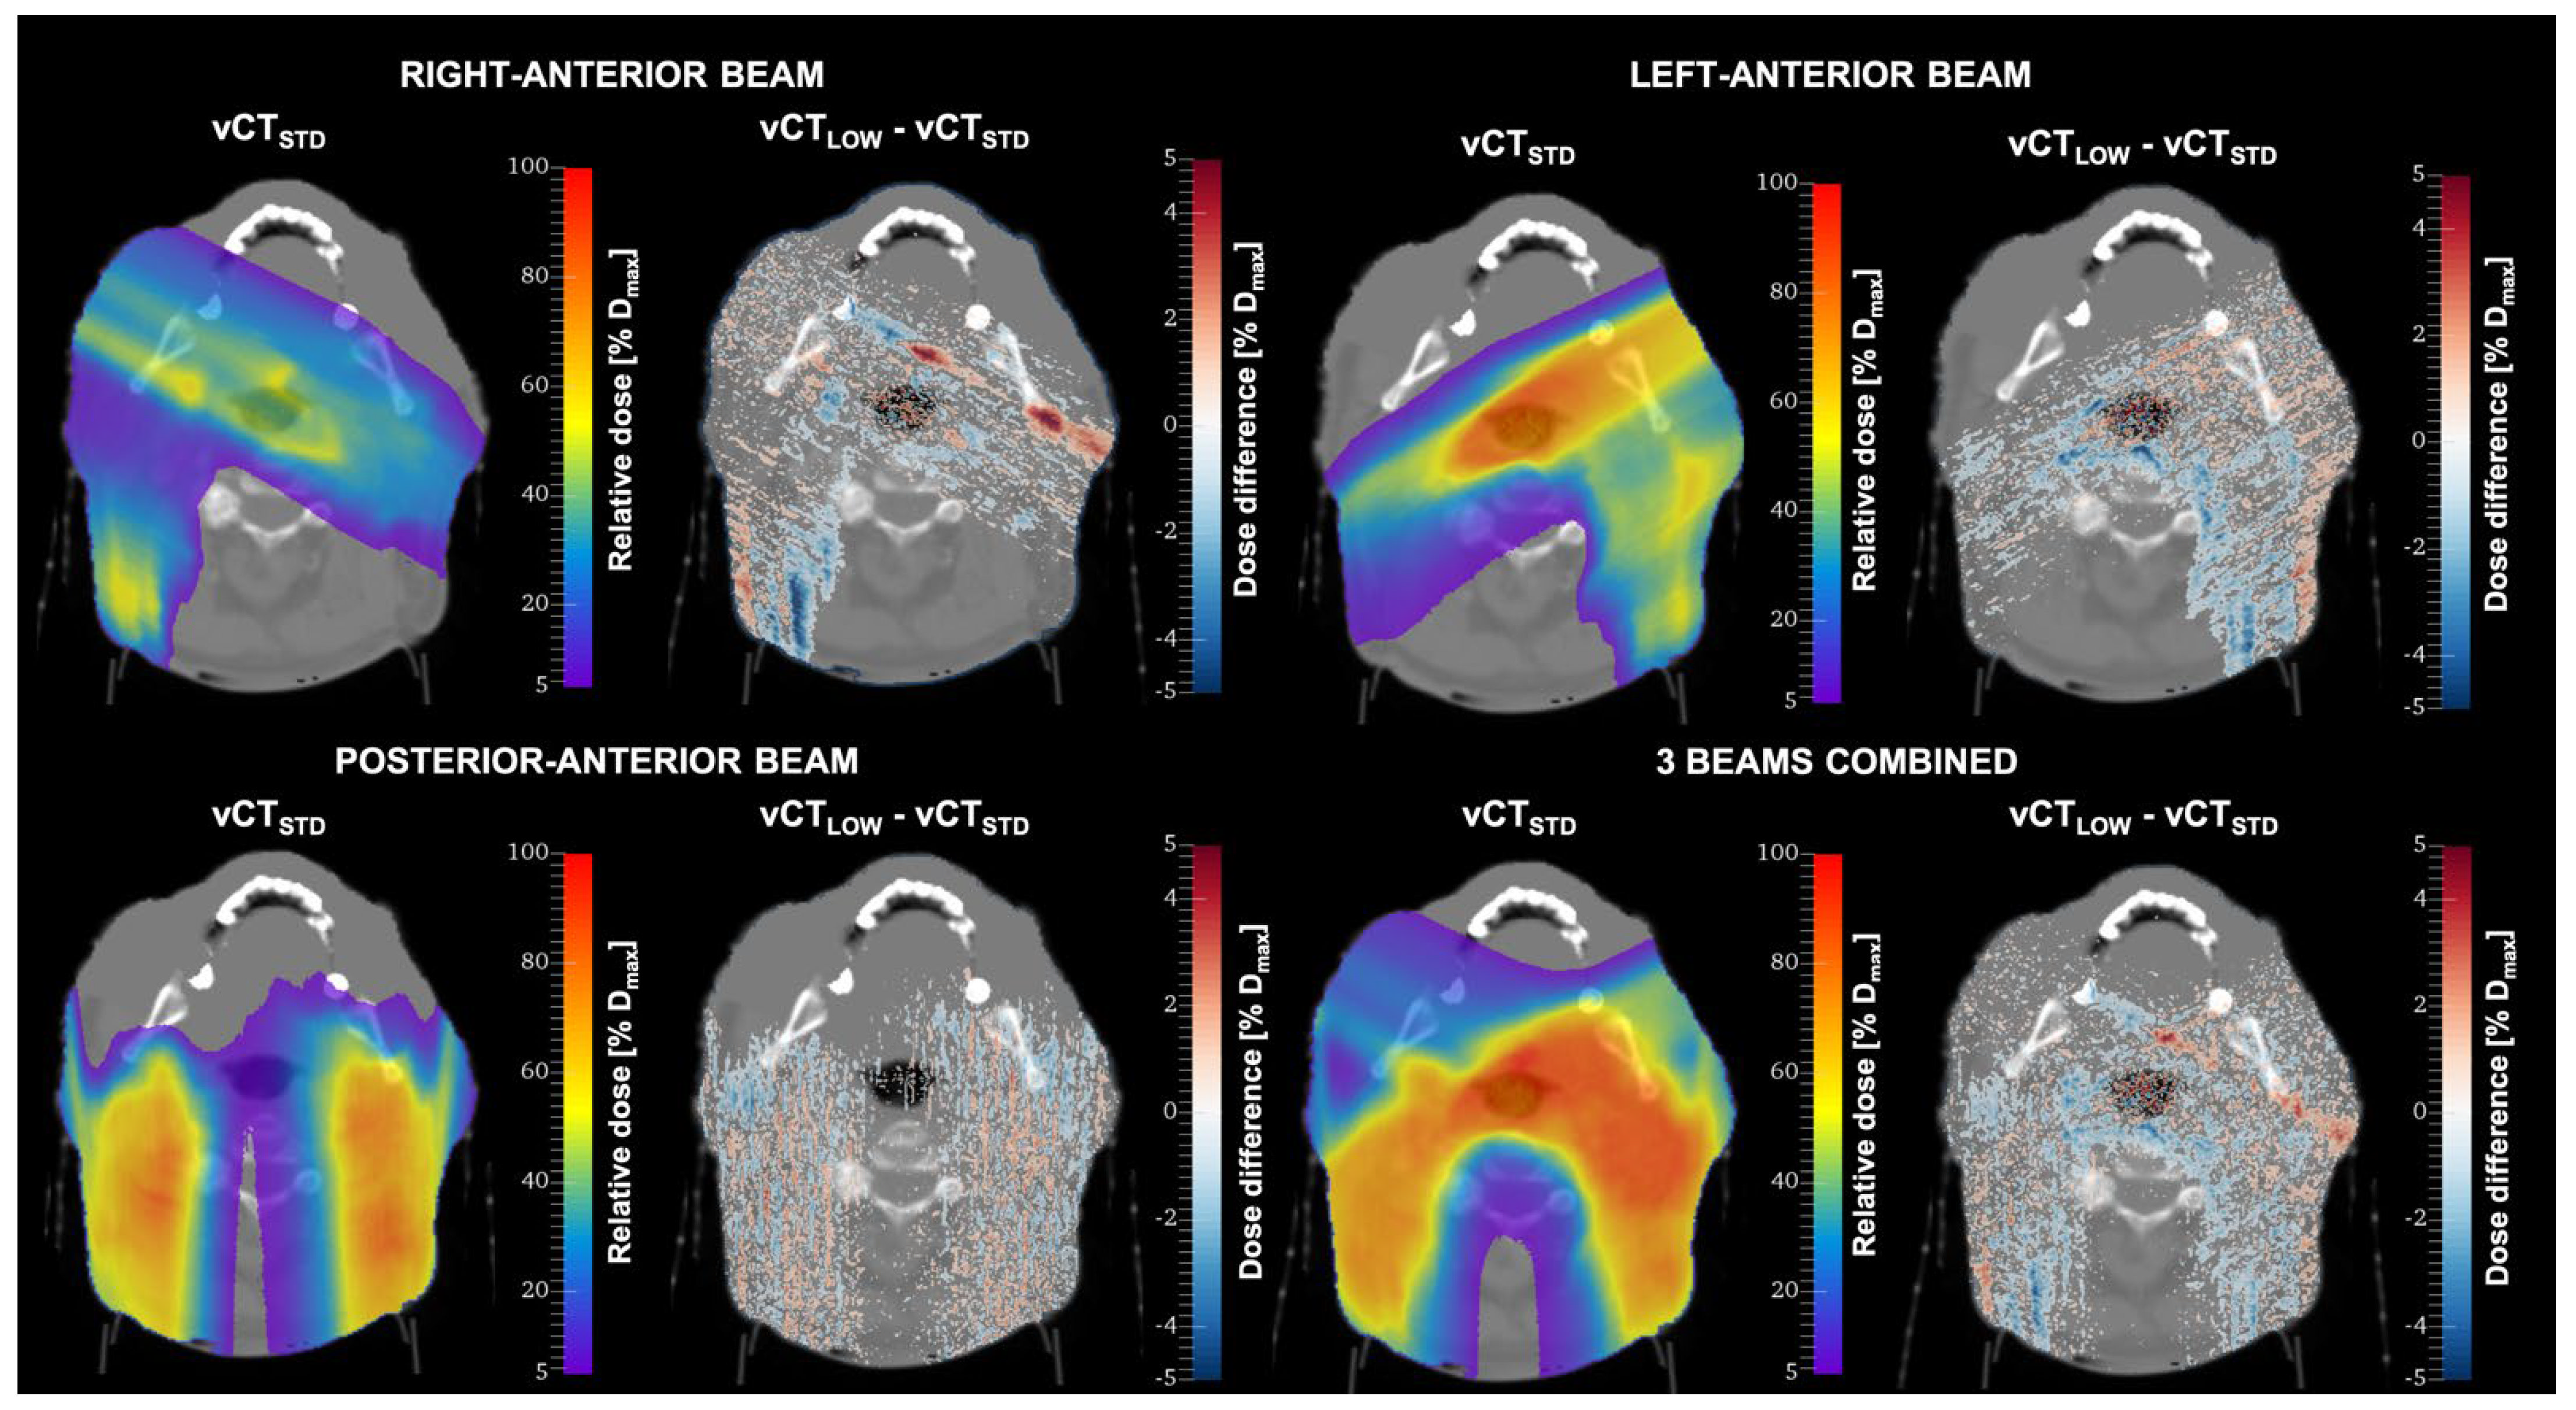

Dose differences between the standard-protocol CT (vCTSTD) and low-dose CT (vCTLOW) for one patient are shown in Figure 10. The vCTLOW corresponds to the protocol with the lowest achievable imaging dose (CTDIvol = 4.2 mGy). Although for single voxels differences of up to 16% of the maximum dose (Dmax) were observed, the vast majority of voxels were within 5% Dmax. The results of 2%/2 mm gamma evaluation pass rates for the whole patient cohort are shown in Table 3. The results show the lack of uncertainties in proton range. This can be explained by the fact that the HU variations may cancel out over the beam path.

Figure 10.

Dose distributions calculated for one patient in standard-protocol CT images (vCTSTD) and the difference between the dose distributions calculated in vCTSTD and low-dose CT (vCTLOW).